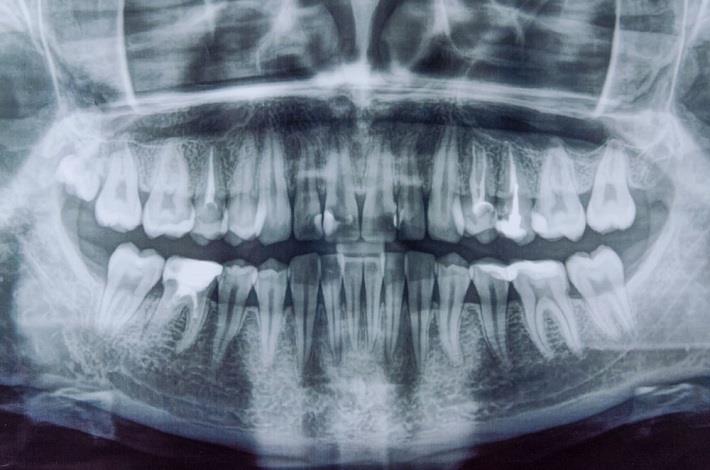

[1] צילום שיניים פנורמי הוא צילום רנטגן שמראה את כל המבנים בפה בתמונה אחת, כולל השיניים העליונות והתחתונות, מפרקי הלסת, העצבים, הסינוסים והעצם התומכת. בצילום רנטגן נעשה שימוש בקרינה אלקטרומגנטית כדי לצלם את החלקים הפנימיים של הפה. קרן הקרינה עוברת דרך הרקמות הרכות של הפה ויוצרת תמונות של השיניים והעצמות. רופאי שיניים משתמשים בצילומי רנטגן כדי לבחון מבנים שהם לא יכולים לראות במהלך בדיקה שגרתית, כמו עצם הלסת, העצבים, הסינוסים ושורשי השיניים. בשונה מצילום רנטגן מסורתי (באמצעות סרט צילום) צילום שיניים פנורמי הוא לרוב דיגיטלי (באמצעות חיישנים דיגיטליים ומחשב) ונעשה שימוש ב-80% עד 90% פחות קרינה בהשוואה למכונות רנטגן מסורתיות.

צילום: shutterstock | ERIK Miheyeu

צילום רנטגן פנורמי מאפשר לרופא השיניים לקבל סקירה כללית של כל חלקי הפה בצורה חדה וברורה, ובכך לאתר בעיות בריאותיות הקיימות בפה. בעזרת צילום פנורמי ניתן לתכנן את תכנית הטיפולים עבור שיניים תותבות, יישור שיניים, עקירות ושתלים[2].

צילומים פנורמיים עוזרים לרופא/ת השיניים לאבחן מגוון רחב של בעיות בריאות הפה כגון[1]:

צילומים פנורמיים מספקים לרופא השיניים מידע חיוני באבחון ובתכנון הטיפול עבור המטופלים/ות. באופן כללי, ניתן לראות את המבנים של מפרק הלסת בצורה טובה יחסית. צילום פנורמי משמש בדרך כלל כבדיקת סקר ראשונית הזולה בהרבה מ-CT או MRI. למרות שלא ניתן לראות שינויים עדינים בבירור בצילומים פנורמיים, ניתן לזהות חריגות של משטחים או מפרקים, כגון שחיקות בינוניות עד חמורות, היווצרות אוסטאופיטים (דלקת במפרקים), ספיגה בשן ושברים. בדיקה זו יכולה לשמש גם ככלי הערכה כללי לשלילת חריגות בלסת העליונה, הלסת התחתונה ובשיניים[4].